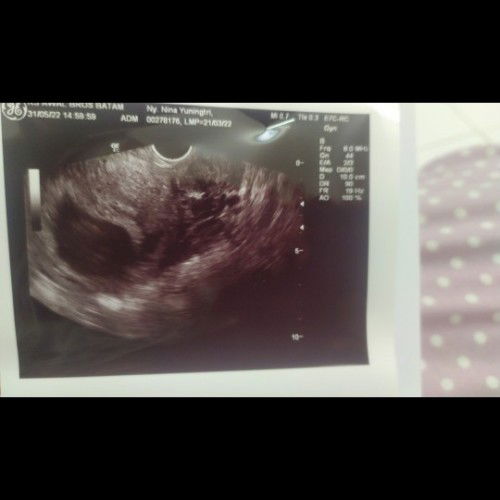

Assalamu'alaykum bunda semua.. saya mau nanya.. ini hamil anak ketujuh saya. Waktu USG pertama kali umur 6-7w (sebelah kanan) nampak bintik (calon janin) wlpn belum ada detak jantungnya. Nah, td siang USG lg di usia kehamilan 10weeks (sebelah kiri), tp dinyatakan BO karna janin tdk terlihat ( beda dokter). Tp coba perhatikan deh, kek ada sesuatu yg samar ya.. kek bentuk janin tp samar bgt.. akhirnya dokter menyarankan kuret. Tp karna saya masih merasakan mual bgt, pusing dan mudah lelah trus jg tidak ada tanda flek, bleeding atau kram perut, jd feeling saya utk tetap menunggu 1-2 pekan lg. Tolong bunda, apa ada punya pengalaman seperti saya? Menunggu 1-2 pekan lagi, dan pas USG janin sudah terlihat? Dgn catatan tdk ada tanda2 keguguran ya.. makasih banyak utk yg jawab dan sharing ya bunda-bunda.. #seriusnanya #bantusharing #ingintahu #pleasehelp